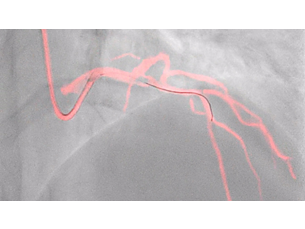

Our imaging technology ClarityIQ, combines advanced, real-time image noise reduction algorithms with state-of-the-art hardware. Together, they form a flexible digital imaging pipeline designed to perform individual image processing algorithms more efficiently. This unlocks superb visualization and significant dose reduction capabilities for healthcare facilities. ClarityIQ is available as an option on Azurion systems.

StentBoost Live

Dynamic Coronary Roadmap